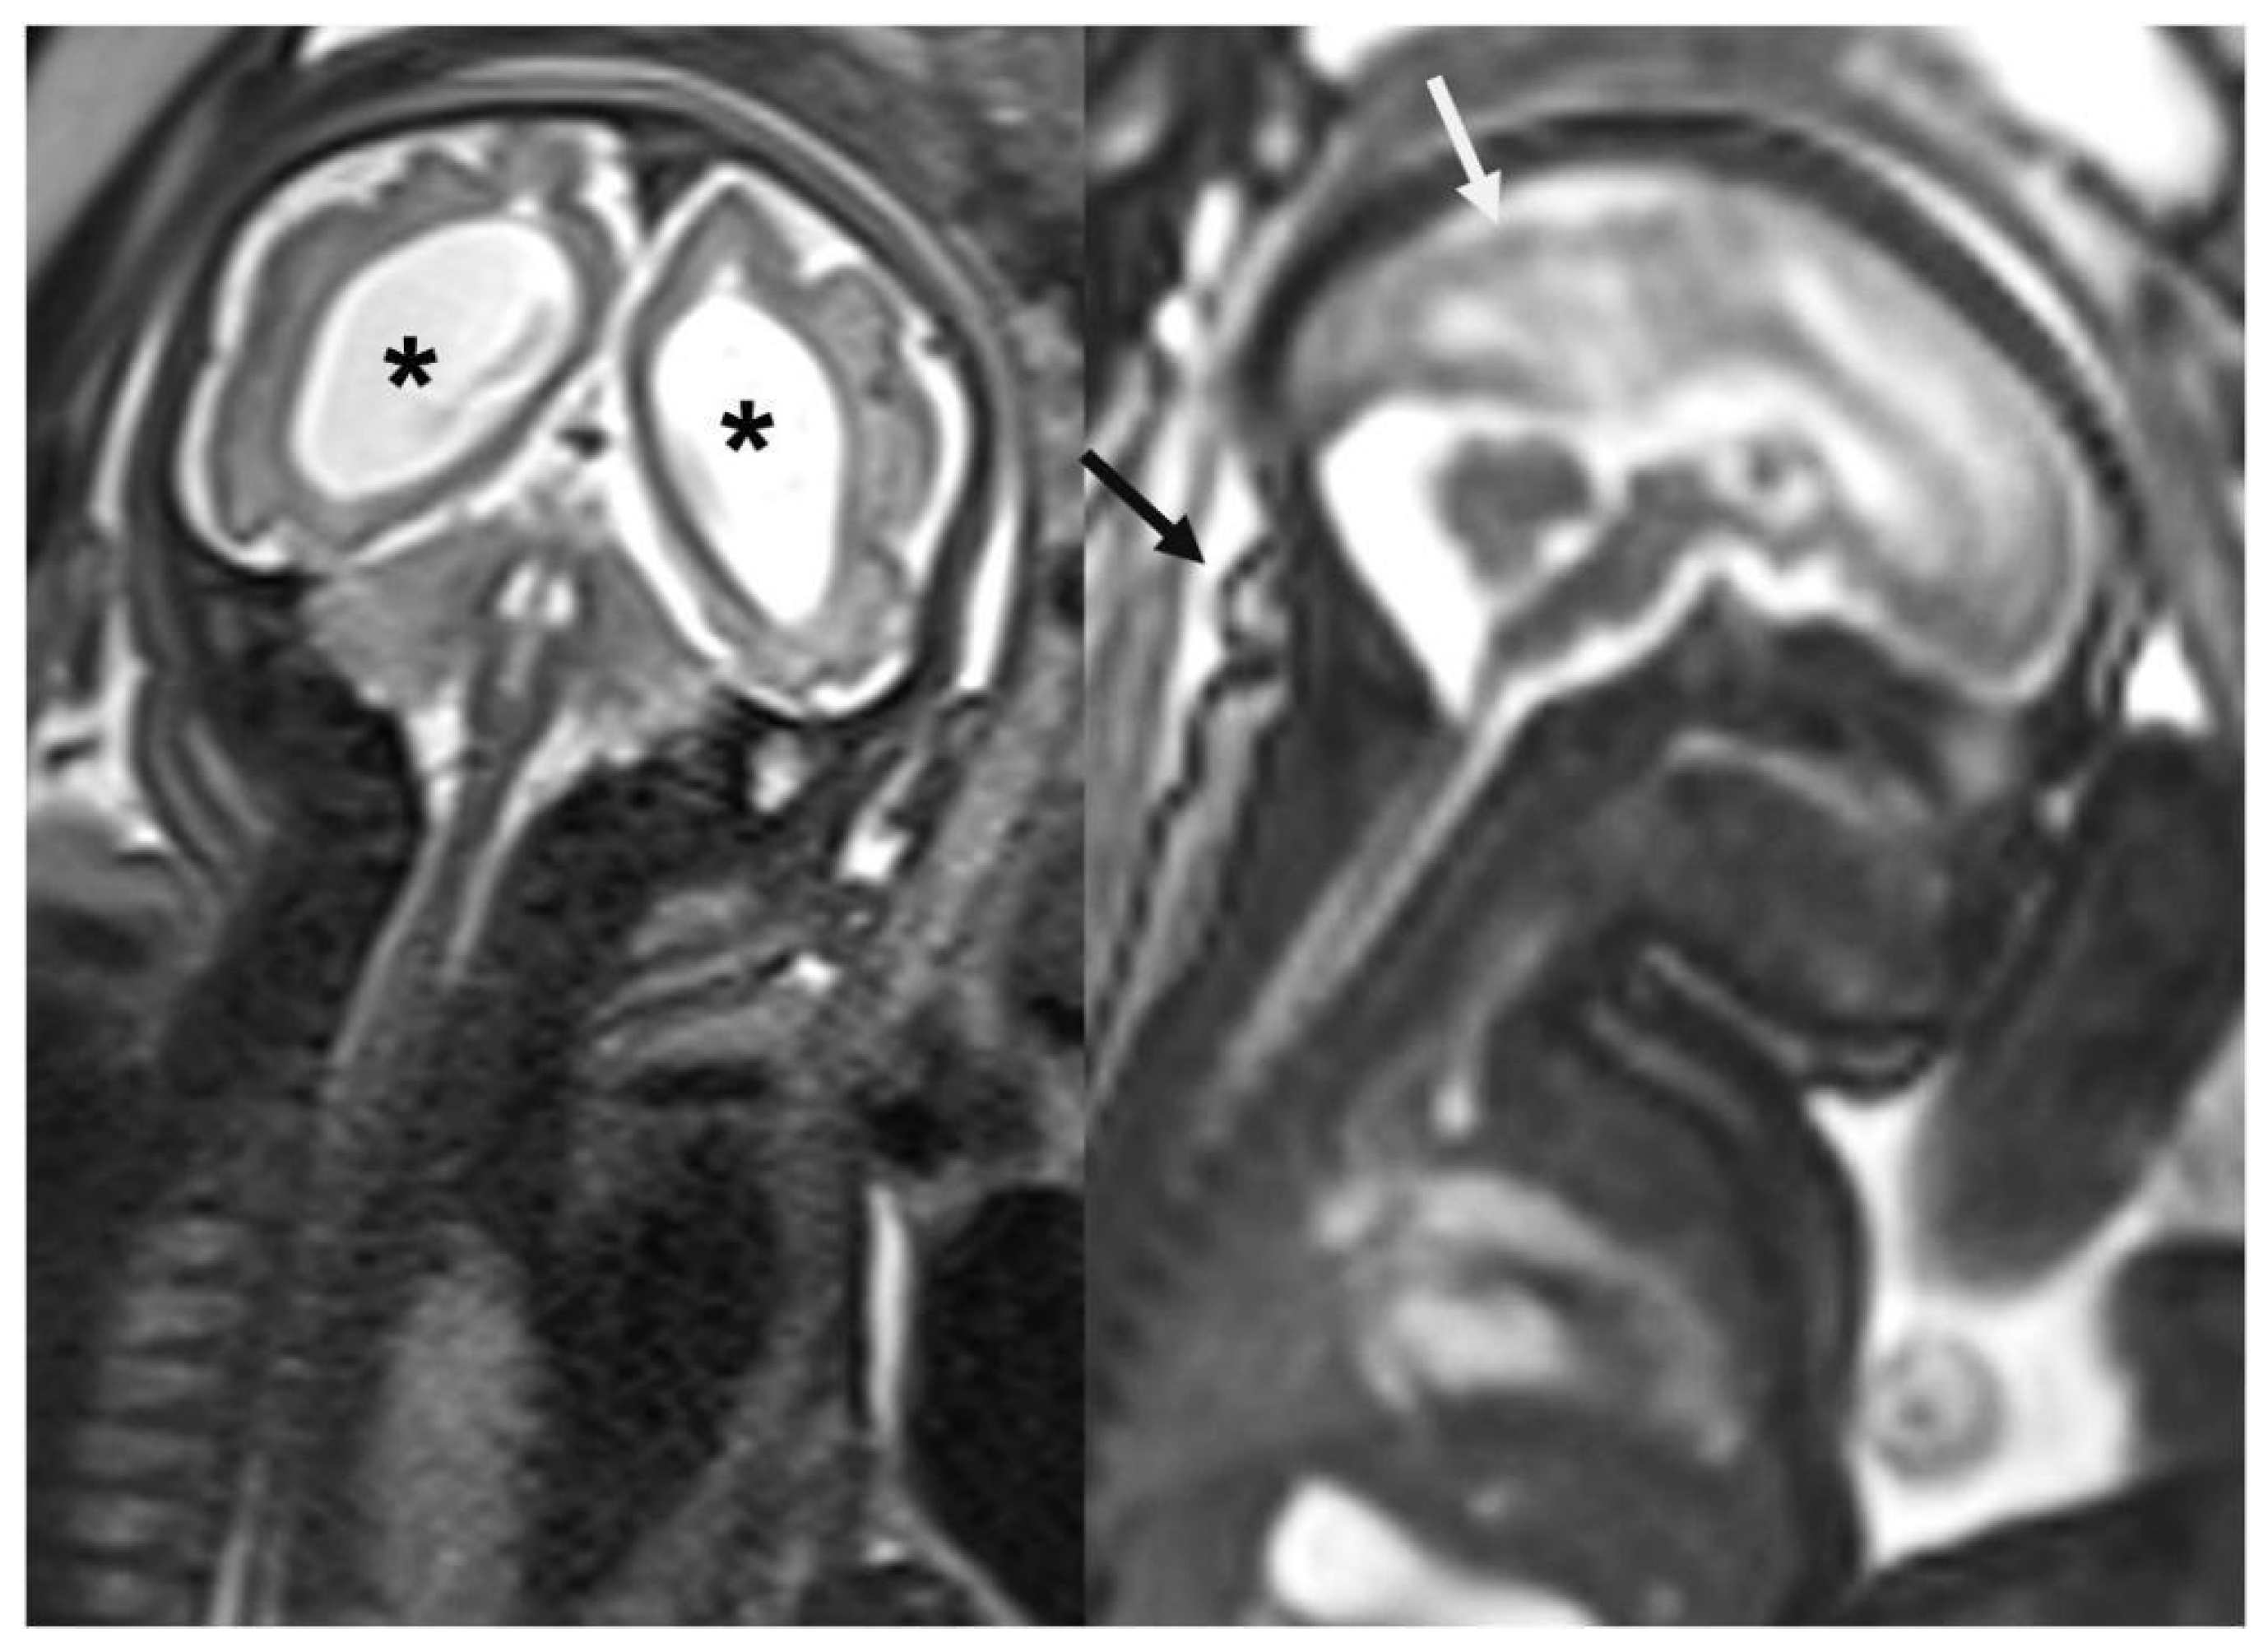

- Araujo Júnior, E.; Carvalho, F.H.; Tonni, G.; Werner, H. Prenatal imaging findings in fetal Zika virus infection. Curr. Opin. Obstet. Gynecol. 2017, 29, 95–105. [Google Scholar] [CrossRef] [PubMed]